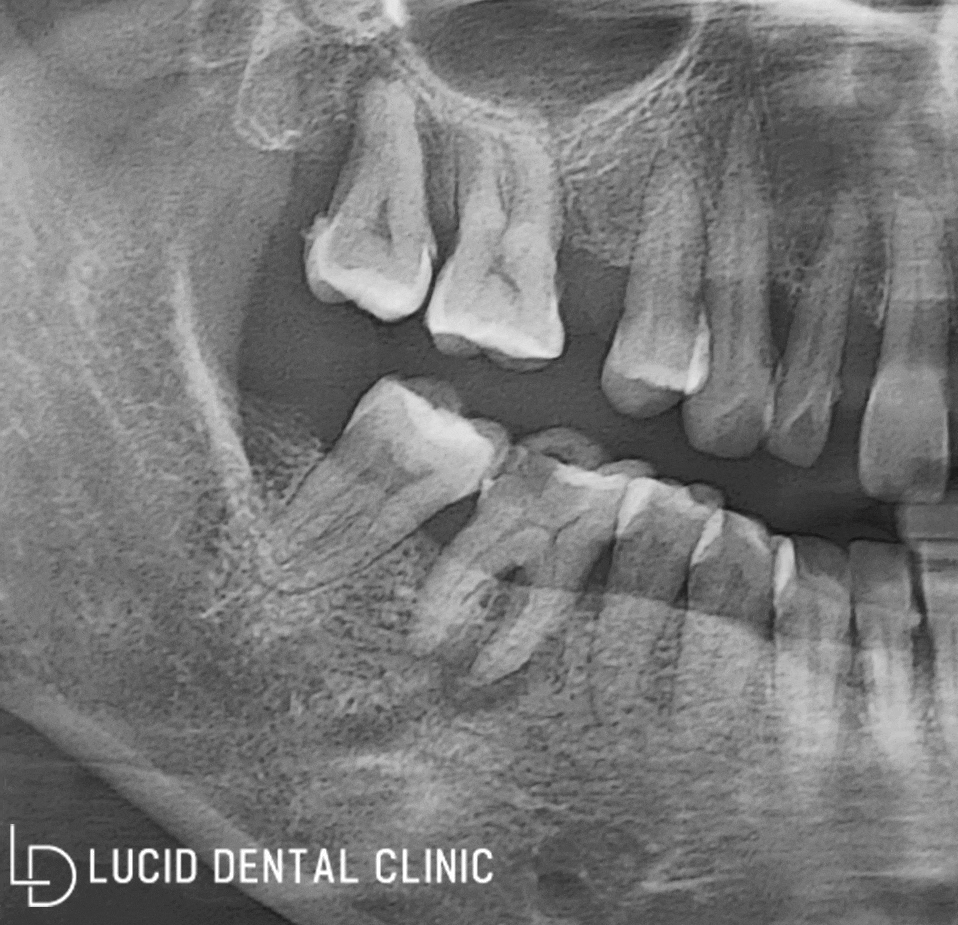

- 과연 검진 결과는?

환자께서 말씀하신 부분을 중점으로

정밀한 구강 검진을 시행한 결과,

다양한 문제점을 발견했습니다.

사진을 함께 보며 설명해 드릴게요.

사진을 기준으로

아래턱 왼쪽 어금니에

(1) 치근단 염증, 다시 말해

뿌리 주위 염증이 나타났고,

(2) 표시해 드린 부분 모두 충치

감염이 심하게 일어났습니다.

이 부분은 오른쪽 어금니

역시 마찬가지였는데요

(3) 심지어 오른쪽 구강은

치아 정출이 일어났으며

교합을 방해하고 있었습니다.

그 이유는, 왼쪽과 오른쪽

모두 발치하고 비어있는 어금니

부분이 있었기 때문이라고 봅니다.

이대로 가다간 다수의 기능을 소실하고,

생활하는 데에 큰 불편이 일어날 것입니다.